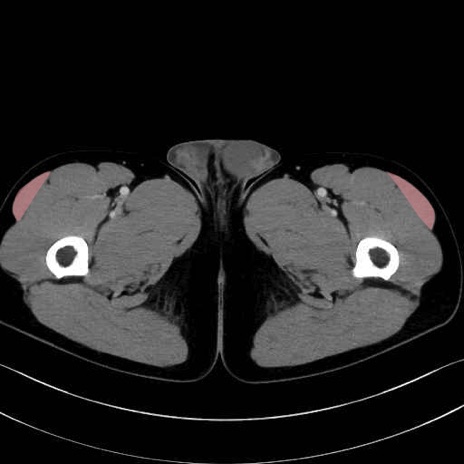

大腿筋膜張筋 (Tensor fasciae latae)